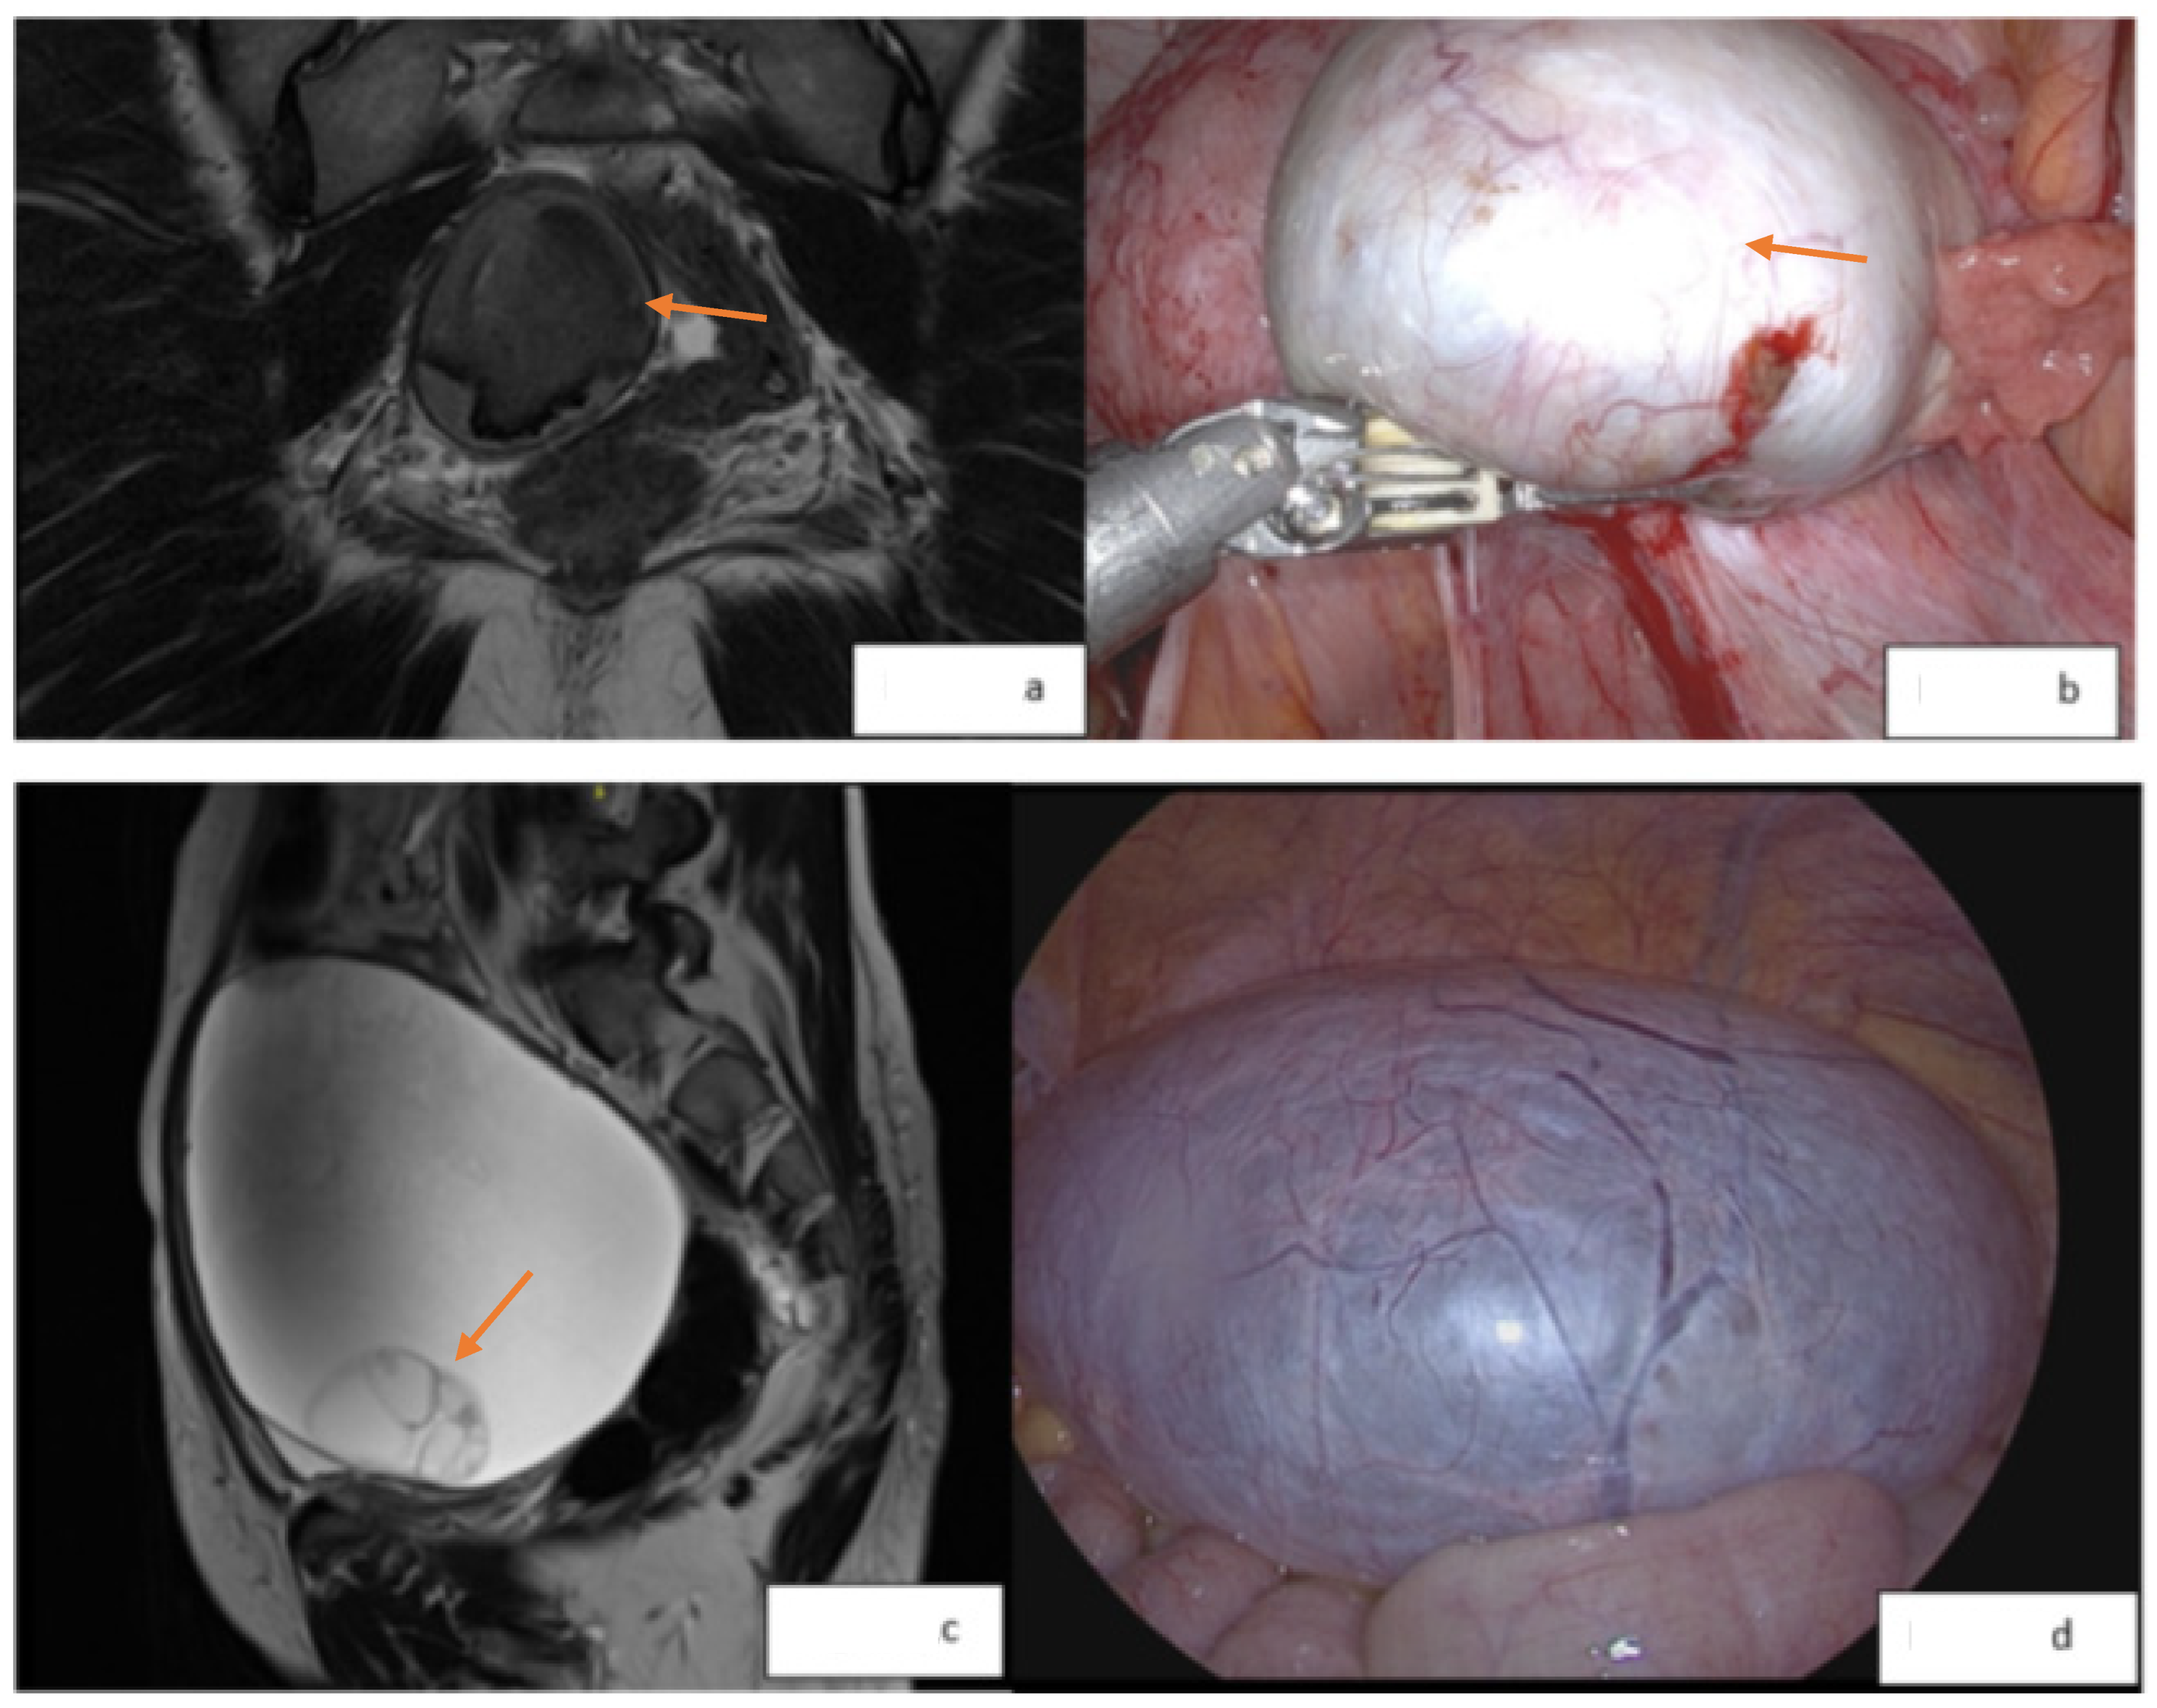

There is also an additional ability to evaluate for atypical features within an endometrioma. The MRI features of endometriosis-associated ovarian cancer (EAOC) include intermediate T2 signal (particularly the loss of T2 shading due to the dilution of hemosiderin within an endometrioma by increased fluid produced by a tumor), solid enhancing mural nodules within an otherwise cystic lesion, irregular and nodular septations, and restricted diffusion on diffusion-weighted imaging (DWI) [31,32]. It is important to remember that these findings are non-specific and may not always be associated with malignancy [33]. Examples of MR images and associated laparoscopic findings from normal and malignant endometriomas are shown in Figure 1.

Figure 1.

(a): O-RADS 2 lesion; 4.7 cm right ovarian endometrioma (orange arrow) with no enhancement, nodularity, or suspicious features. (b): Laparoscopic image (orange arrow indicating lesion); pathology consistent with endometriosis. (c): O-RADS 3 lesion; increasing size and complexity of a right adnexal mass measuring 13.5 cm (orange arrow indicating the areas of septations). (d): Laparoscopic image; pathology consistent with the grade 1 endometrioid adenocarcinoma of the ovary.